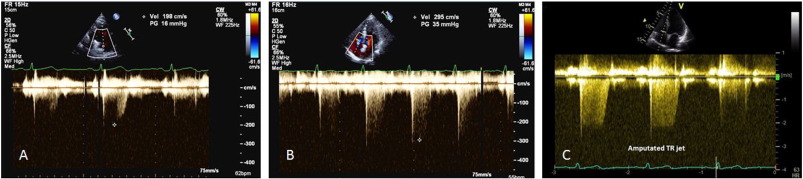

A coaxial TR jet is identified in parasternal long axis (RV inflow), parasternal short axis, or apical 4-chamber view with the help of colour Doppler. CW Doppler is used with a sweep speed of 100 mm/s to achieve a satisfactory envelope (Fig. 1 ). The peak velocity of the envelope is then measured (TRmax ). A value of ≤ 2.8 m/s suggests low probability, a value of 2.9–3.4 m/s indicates intermediate probability, and a value > 3.4 m/s suggests a high probability for pulmonary hypertension [1] . Traditionally, right atrial pressure (RAP) is assumed by the size and distensibility of inferior vena cava (IVC) during inspiration at rest and during forced inhalation, and this value is added to the peak TR velocity [8] . However, recent ESC guidelines suggest just using the TRmax without additional RAP, as IVC assessment is error prone [1] . Mean PAP can be approximated from the systolic PAP (SPAP) using the following formula: mPAP = 0.61*SPAP + 2 mmHg [9] .

TR Vmax method for measuring PASP.

A lesser degree of TR may occur in a compensated right ventricle (due to elevated ventricular pressure) and this could lead to underestimation of PASP. Similarly, severe TR could cause equalisation of right atrial and ventricular pressures which may cause the TR Doppler envelope to be cut short, leading to underestimation of PASP (Fig. 2 -C) [8] . RAP is often overestimated if IVC measurement is used, leading to overestimation of PASP [10] . Calculations using the TR trace assume that there is no pulmonary valve stenosis and may be inaccurate in the presence of RV systolic dysfunction. TR signal could be poor in a good proportion of patients with lung disease, and TRmax measurement should be avoided in the absence of a good Doppler envelope (Fig. 2 ) [11] .

Fig. 2.

Pitfalls in TR peak measurement.

A, B—Peak TR measurement with incomplete trace could lead to underestimation.

C—Amputated jet could occur in severe TR that could lead to underestimation.